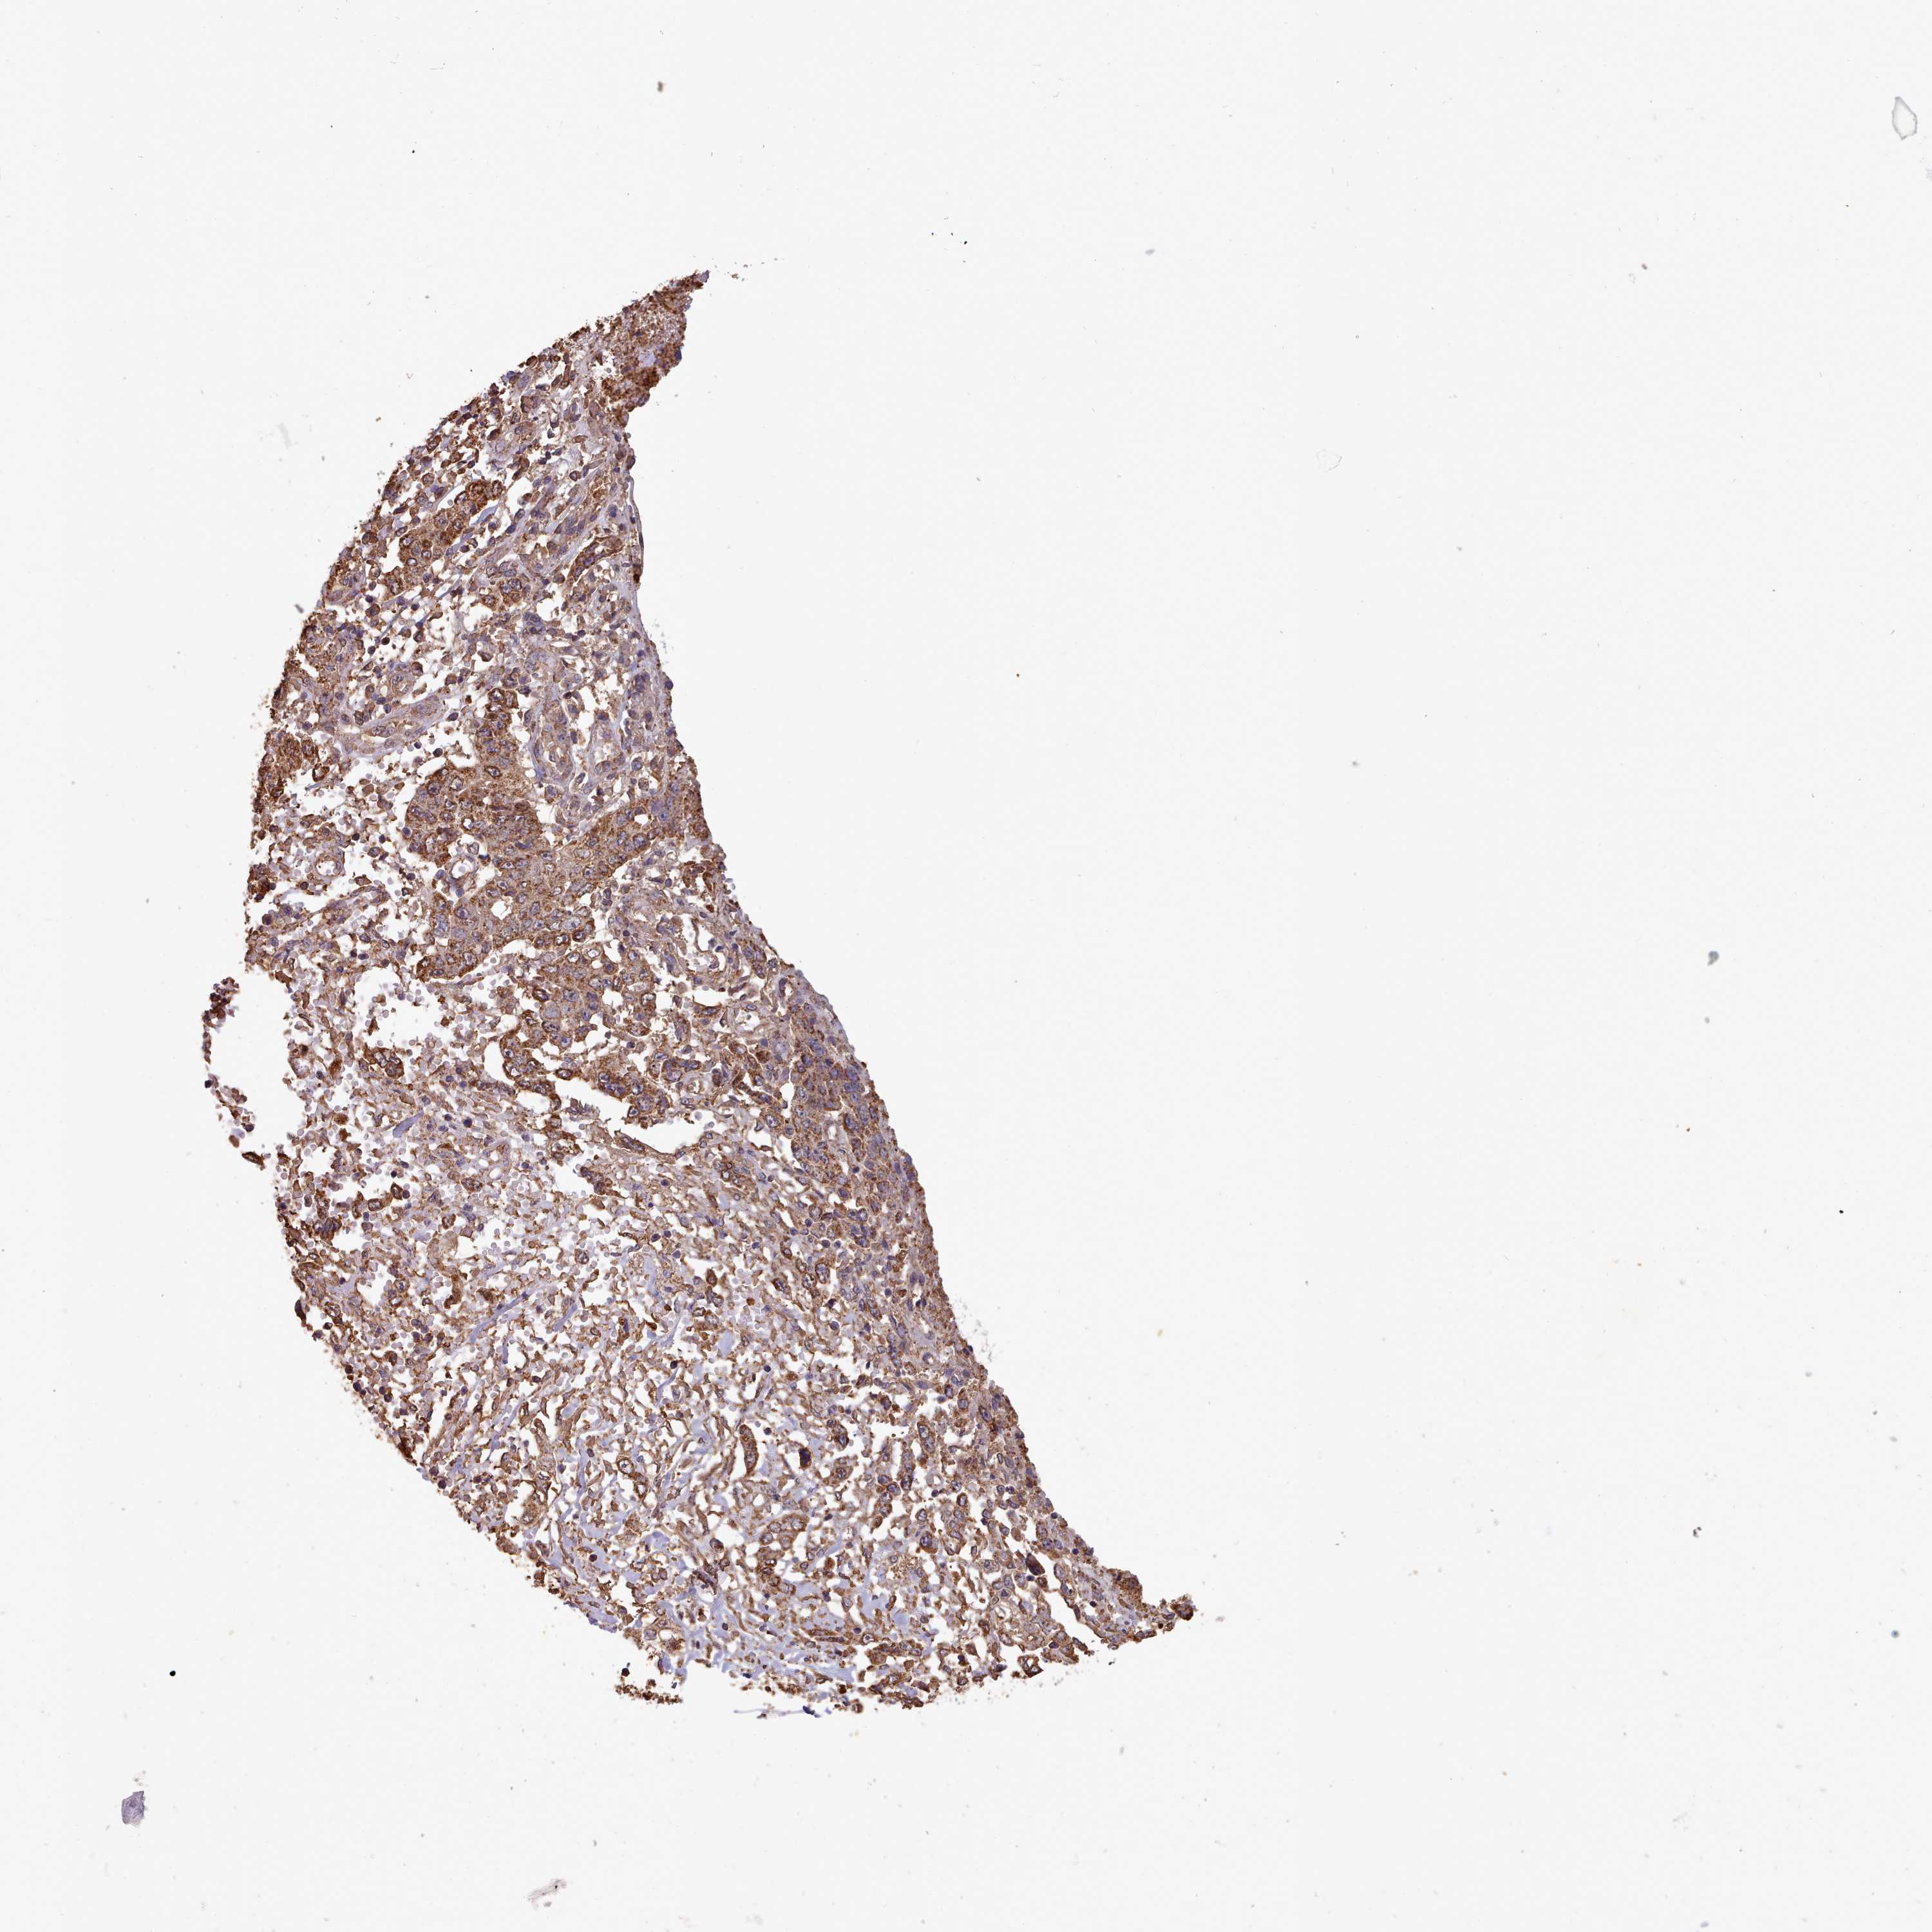

STOMACH CANCER - Protein expressioni

A mouse-over function shows sample information and annotation data. Click on an image to view it in a full screen mode. Samples can be filtered based on level of antibody staining by selecting one or several of the following categories: high, medium, low and not detected. The assay and annotation is described here.

Note that samples used for immunohistochemistry by the Human Protein Atlas do not correspond to samples in the TCGA dataset.

Antibody stainingi

Antibody staining in the annotated cell types in the current human tissue is reported as not detected, low, medium, or high, based on conventional immunohistochemistry profiling in selected tissues. This score is based on the combination of the staining intensity and fraction of stained cells.

Each image is clickable and will lead to virtual microscopy that enables deeper exploration of all samples and also displays staining intensity scores, fraction scores and subcellular localization as well as patient and tissue information for each sample.

Antibody HPA051164

Staining

High

Medium

Low

Not detected

Intensity

Strong

Moderate

Weak

Negative

Quantity

>75%

75%-25%

<25%

None

Location

Nuclear

Cytoplasmic/membranous

Cytoplasmic/membranous,nuclear

Adenocarcinoma, NOS